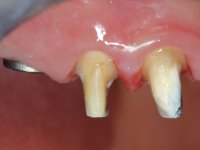

Paciente do sexo feminino, com 43 anos, não fumadora. Após exame clínico e imagiológico, verificou-se que apresentava no maxilar superior os dentes 1.7/1.4/1.3/2.2/2.3/2.4/2.6 com tratamento endodôntico, apresentava a ausência dos dentes 1.6/1.5/1.2/1.1/2.1 e 2.5 e estava reabilitada com uma ponte metalo-cerâmica de 10 elementos em monobloco. A zona anterior da maxila apresentava-se com extensa reabsorção óssea vertical e vestibular. No maxilar inferior, tinha dois implantes colocados no local dos dentes 4.6 e 4.5 reabilitados com uma ponte metalo-cerâmica. Os dentes 3.6 e 3.7, com tratamento endodôntico, estavam reabilitados com postes intra-radiculares e uma ponte metalocerâmica de dois elementos. Os dentes antero inferiores apresentavam restaurações de resina composta, tipo classe III e IV. O dente 3.5 estava ausente. A paciente apresentava uma redução da dimensão vertical da oclusão, acompanhada por acentuado desgaste dentário e algumas fraturas de cerâmica. Boa higiene oral.

Foram realizadas impressões em alginato a ambas as arcadas, acompanhadas pelo registo das relações inter-maxilares e recolha de informação com arco facial. No laboratório foi confecionada uma ponte provisória de 13 elementos em acrílico autopolimerizável na qual foi incorporado um reforço metálico. Os dentes 1.7/1.4/1.3/2.2/2.3/2.4 e 2.6 foram utilizados como pilares. A ponte metalo-cerâmica foi removida após a realização de cortes longitudinais feitos com brocas diamantadas. Os preparos dentários foram re-preparados e a ponte provisória foi rebasada em boca com acrílico auto-polimerizável. Após a confeção da ponte provisória, foi confecionada uma epítese gengival em resina composta com tonalidade gengival, com o objetivo de funcionar como uma maquete, que permitisse à paciente pré visualizar a possibilidade de utilização de cerâmica de tonalidade gengival no trabalho final. Esta opção foi aprovada como válida pela paciente. Posteriormente foi planeada e executada a colocação de dois implantes no primeiro quadrante. O monobloco provisório foi retirado para a colocação dos implantes e após a cirurgia foi novamente cimentado provisoriamente. Passado o período de osteointegração foram realizadas as impressões ao maxilar superior. Na zona anterior foram utilizados fios de afastamento gengival impregnados e nas zonas posteriores foi utilizada pasta de caolino. A impressão aos implantes utilizou a técnica de moldeira aberta. O material de impressão utilizado foi o silicone de adição putty soft e regular, ambos de presa rápida. No laboratório, o modelo das restaurações provisórias e a maquete em resina serviram de orientação ao enceramento da infra-estrutura. O modelo de trabalho em gesso e o enceramento da infraestrutura foram colocados num scanner laboratorial e deram origem a um modelo de trabalho digital no qual foi sobreposta a digitalização da infraestrutura encerada. Esta sobreposição facilitou o desenho CAD da infraestrutura em Zr. Posteriormente, o desenho CAD por um processo CAM de fresagem deu origem às peças de Zr. A infraestrutura foi pigmentada com uma coloração rosada, que favorecesse a colocação posterior de cerâmica de tonalidade gengival. Durante a modelação da infraestrutura foi detetada a necessidade de aumentar o desgaste oclusal no dente 1.4. Este desgaste foi feito no modelo de trabalho real e foi confecionada uma guia de controlo de desgaste em acrílico que acompanhou a prova das infraestruturas. Em boca foi realizado o desgaste corretivo e foi realizada a prova das peças de Zr. Durante a prova foi reavaliada a escolha da cor da cerâmica de tonalidade gengival. O tratamento foi finalizado no laboratório e após aprovação pela paciente foi colocado definitivamente em boca.